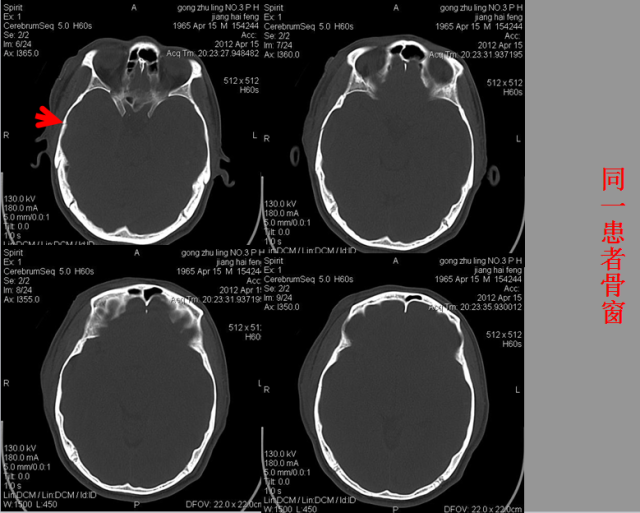

急性颅脑损伤篇

03